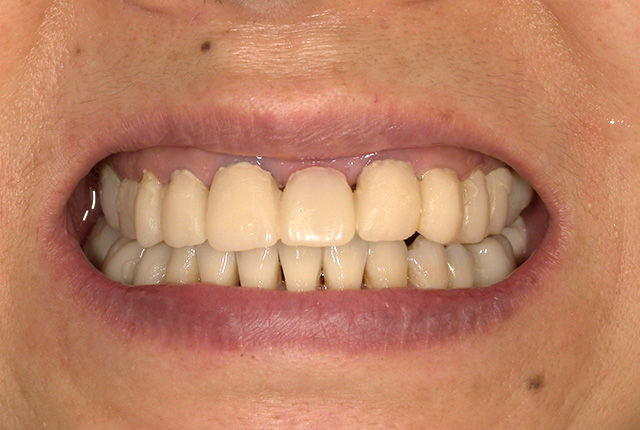

よく噛めず笑うと銀歯が目立つので気にされていました。

90分の治療で銀歯の状態からキレイな状態になります。噛み合わせの調整や審美面も使用しながら合わせます。

良く噛めて安心と、ご満足いただき大変嬉しく思います。笑顔も一層素敵になりました。